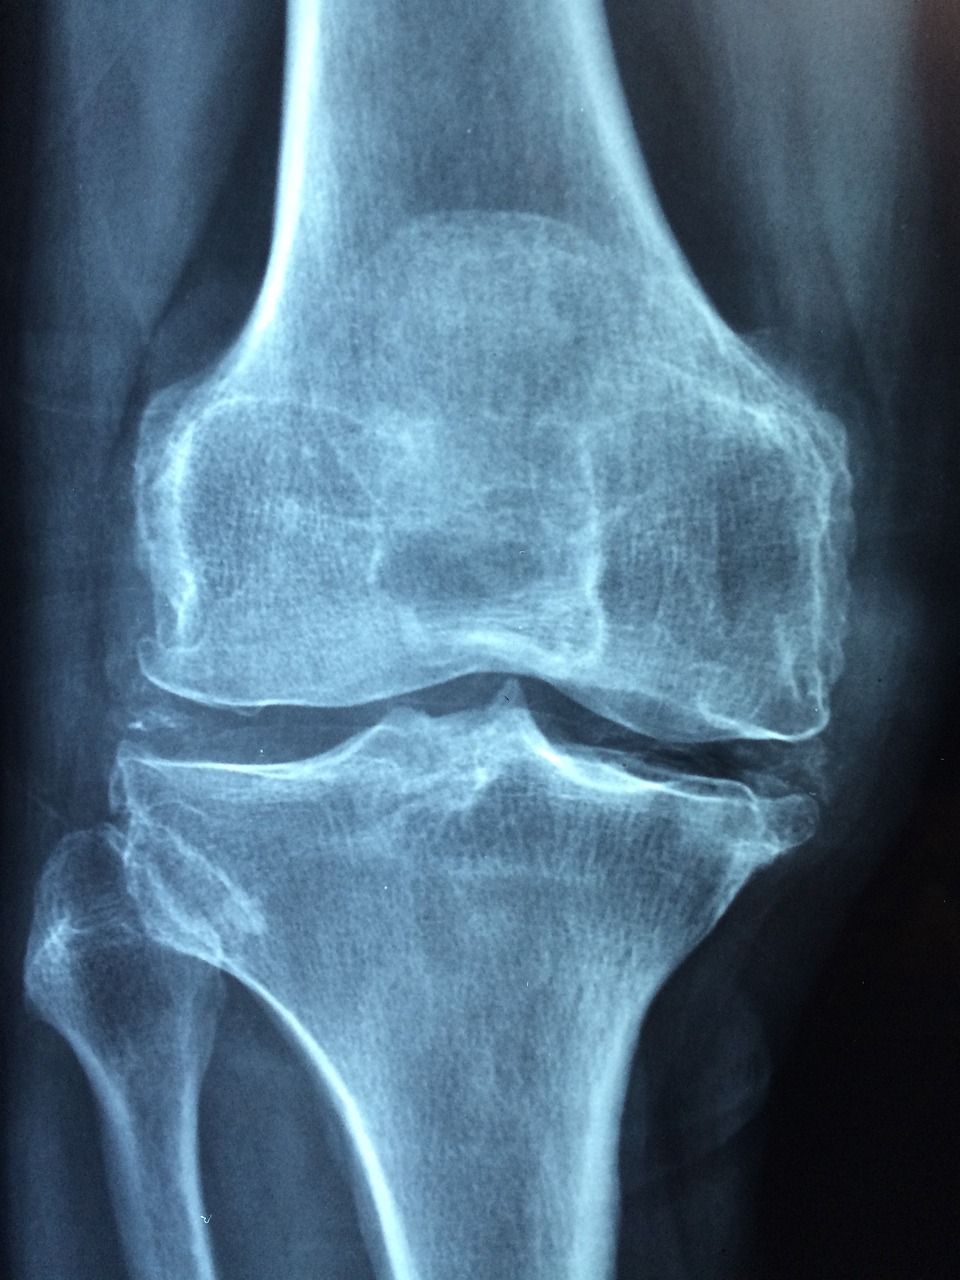

• Az artrózis (ízületi porckopás) főként idősebb korban alakul ki.

Tévhit: Az artrózis gyógyítható

Tény: Jelenleg sajnos nincs olyan gyógyszer, amellyel az artrózis gyógyítható lenne, a porckopás nem szüntethető meg, és ha már kialakult, a károsodás nem fordítható vissza. Azonban sokat tehetünk a betegség súlyosbodásának lassítása és a tünetek enyhítése, valamint a mozgásképesség javítása érdekében. A megfelelő terápiát (gyógyszeres kezelést vagy műtéti eljárást, esetleg porcerősítő étrend-kiegészítőt) alkalmazva a beteg életminősége javítható, fájdalmai enyhíthetők.